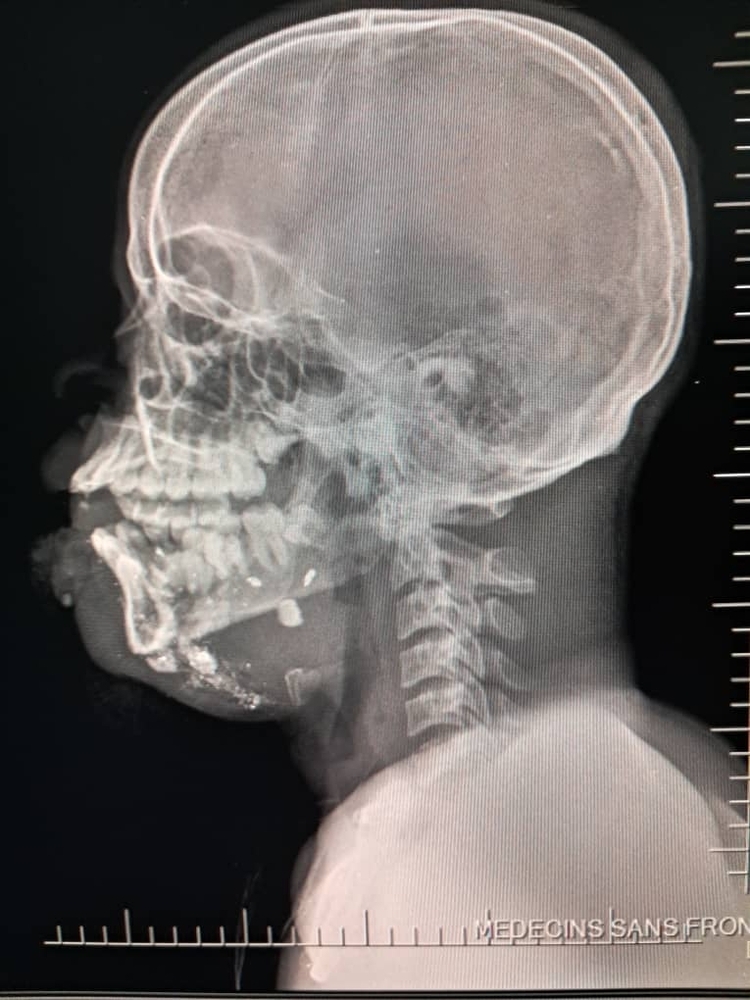

Between January and June 2025, MSF teams assisted 2,600 survivors of sexual violence, admitted 13,300 patients to emergency rooms and treated 2,267 survivors of violence. Among these, 26 per cent were minors, compared to 11 per cent in 2024. Most minors were under the age of 15 and one third were girls. Thirty per cent of all minors admitted for violence-related injuries suffered gunshot wounds.

On Sept. 20, 17 wounded people were treated at the MSF hospital in Drouillard following a drone attack carried out the same day in the Cité Soleil neighbourhood. Among them were two men who were dead on arrival, another man who died while being transferred, 10 women — one of whom died on the way to MSF’s trauma hospital in Tabarre — and three children who tragically did not survive their injuries. Two more women injured in this attack died at the nearby Isaïe Jeanty maternity hospital, where MSF is also working.

This violence is occurring in the context of a territorial conflict with the people directly on the frontlines, trapped between the threat of explosive drones and the brutal violence of armed groups. These groups loot and burn homes, destroy neighbourhoods, terrorize communities and increasingly use sexual violence as a weapon of control, punishment and extortion.